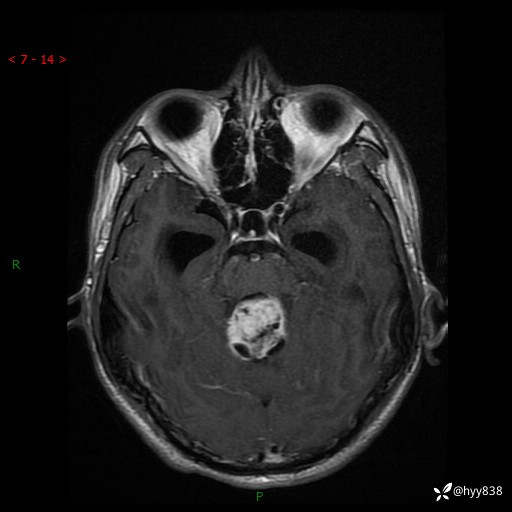

病例花季少年,头痛伴间断性呕吐1月余。四脑室占位,容易诊断错---结果公布~

性别:男

年龄:17岁

简要病史:头痛伴间断性呕吐1月余,外院CT提示颅脑占位

颅脑MRI平扫+增强